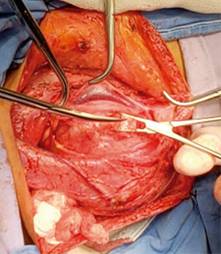

A la exploración física dirigida hay presencia de tumor cervical de 12 × 8 × 10 cm aproximadamente, indurada fija a planos profundos, que abarca región II, III y Va de hemicuello izquierdo (Figura 1), ligeramente dolorosa a la palpación 3/10 EVA, sin dificultad a la apertura bucal, sin datos de asimetría facial y sin compromiso de vía respiratoria.

Se hace protocolo de estudio y se programa para tiempo quirúrgico; en mesa de operaciones con paciente en decúbito supino con posición de Rossier se realiza cervicotomía mediante incisión cervical de Paul André, disecando por planos (piel, tejido celular subcutáneo, platisma) ubicando músculo esternocleidomastoideo, el cual se refiere encontrando detrás del mismo una tumoración localizada en espacio parafaríngeo situada entre vena yugular interna y arteria carótida (Figura 5), la cual se diseca siendo enucleada, se realiza una meticulosa disección subcapsular buscando así preservar las funciones del nervio de origen aparente, el X par craneal, evitando la resección de éste. Dicha pieza es enviada a patología, se realiza hemostasia, se coloca drenaje cerrado de presión negativa tipo Drenovac de 1/8 y se cierra por planos cerrando fascia con Vicryl 2-0 y afrontando piel con nylon 3-0 punto intradérmico, dando por terminado evento quirúrgico.